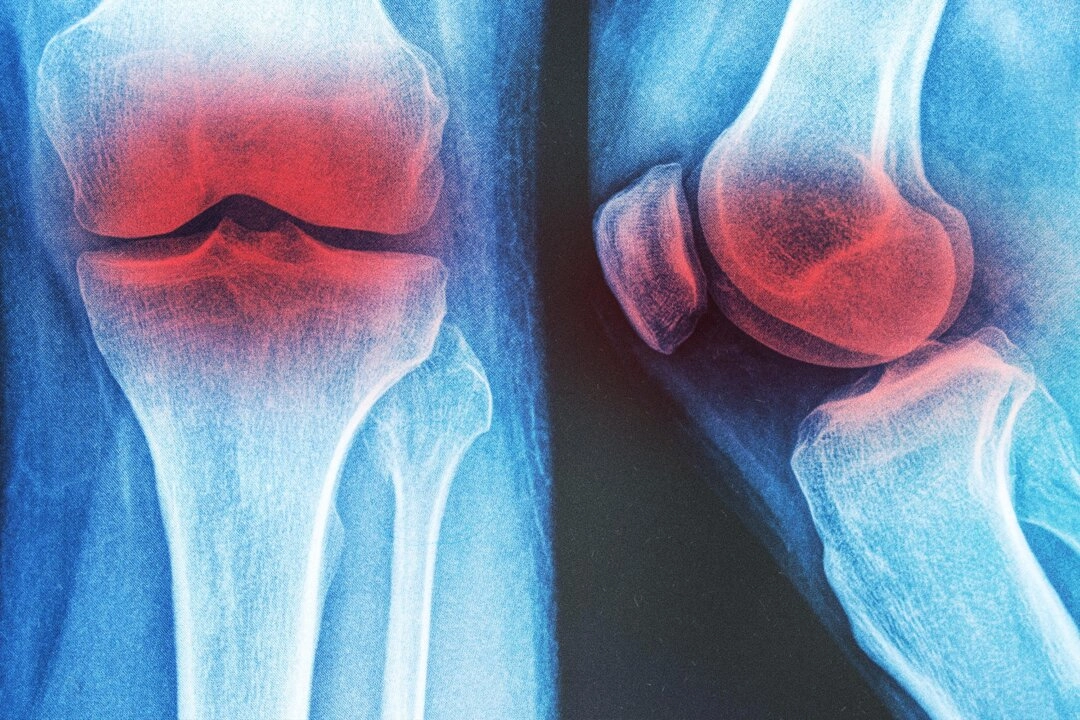

膝關節炎是老年人常見的退化性疾病,在60歲以上人群中,約有10%的男性與13%的女性受到影響。除了疼痛和僵硬,許多患者還會因肌力衰退而喪失行動能力,甚至不能生活自理。

《PLOS One》發表了一項針對膝關節炎的網絡統合分析,評估了12種物理治療干預方式,研究發現其中三種效果突出: